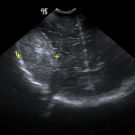

A 71-year-old woman came to the clinic with concern for worsening abdominal distention, shortness of breath when walking, and swelling of her legs.

02/21/2020